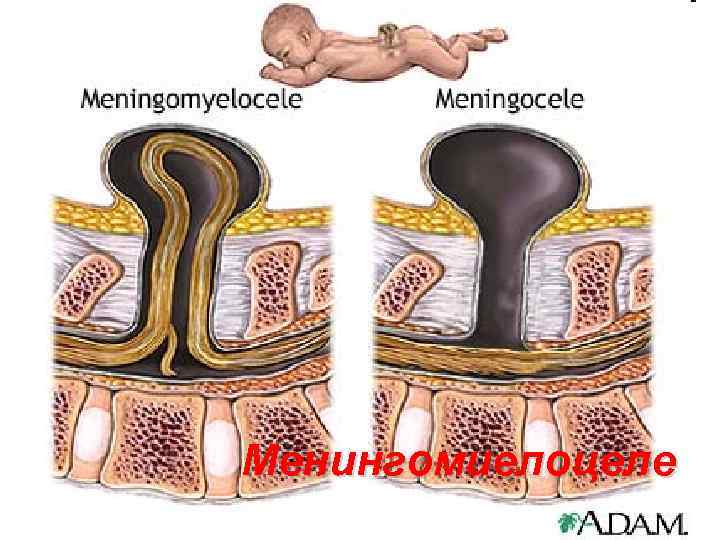

SPINA BIFIDA 111

Менингорадикулоцеле 112

Менингомиелоцеле 113